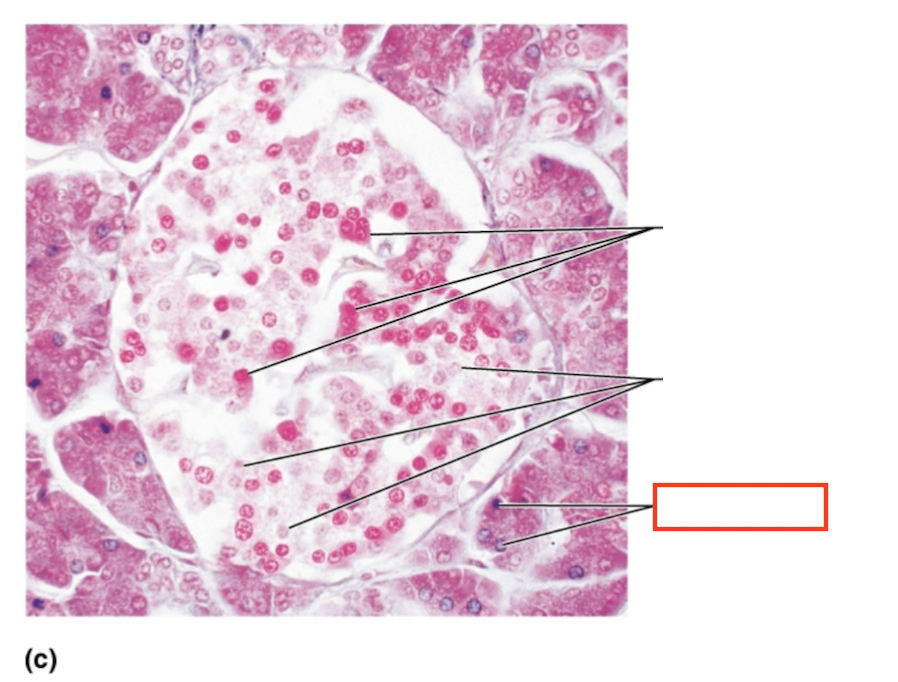

What structure is highlighted?

alpha cells (glucagon producing)

What structure is highlighted?

beta cells (insulin producing)

What structure is highlighted?

pancreatic acinar cells (exocrine)

What tissue is shown?

pancreatic islet

What hormones are released by the pancreas?

insulin, glucagon

What are the target organs and effects of insulin

most cells of the body, accelerates the transport of glucose into body cells; promotes glycogen, fat, and protein synthesis

What are the target organs and effects of glucagon?

primarily the liver and adipose; accelerates the breakdown of glycogen to glucose, stimulates the conversion of lactic acid into glucose, releases glucose into the blood from the liver

What stimulates glucagon production?

decreased blood glucose levels, sympathetic nervous system stimulation

What stimulates insulin production?

increased blood glucose levels, parasympathetic nervous system stimulation